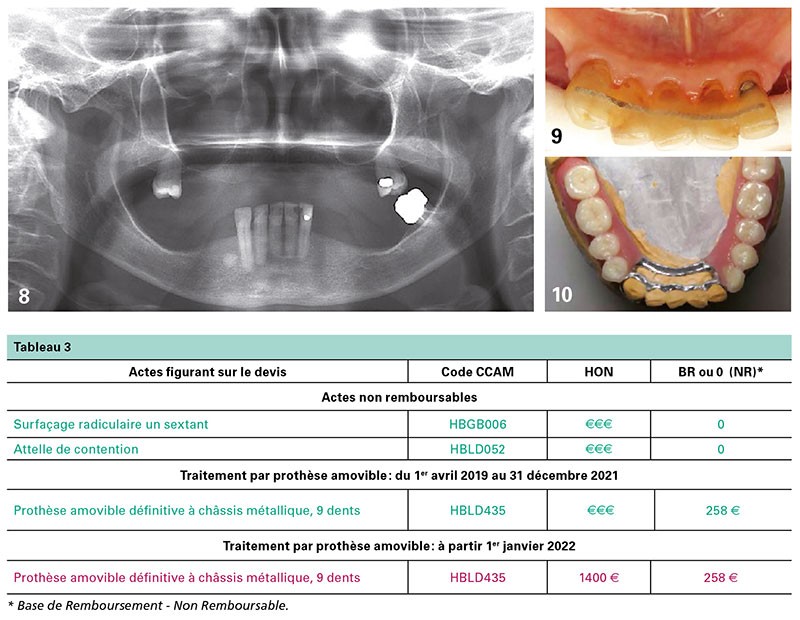

Une patiente, âgée de 76 ans, a une prothèse maxillaire squelettée de 12 dents, satisfaisante (fig. 8 à 10).

La prothèse mandibulaire est cassée. Le traitement prothétique à proposer ne peut ignorer l’état des dents résiduelles : 38 est à extraire et le bloc antérieur doit être assaini.

Sa consolidation et sa maintenance doivent être assurées pour optimiser une rétention non iatrogène de la prothèse amovible (tableau 3).